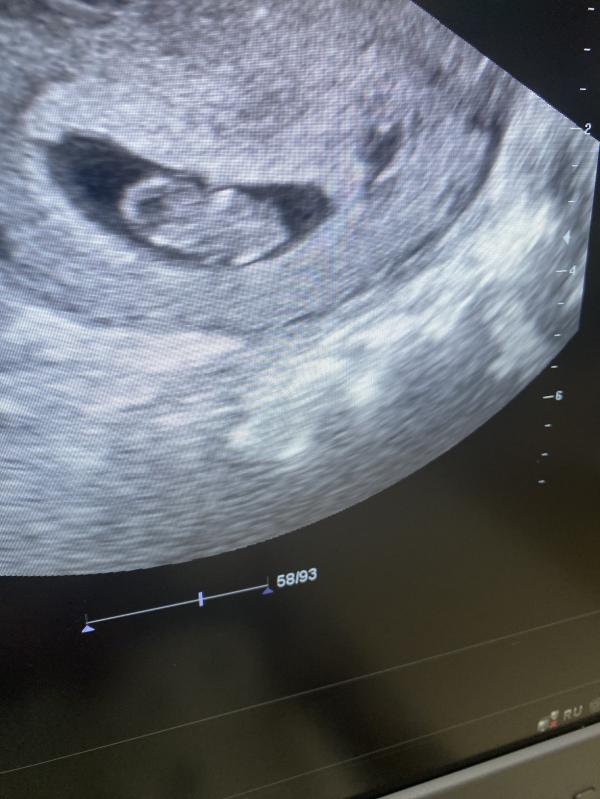

Добрый день 🤍 , на первое узи , что бы послушать сердцебиение есть или нет могу пойти в 6.2?

Рановато, если все спокойно и нет в анамнезе внематочных и нет болей и выделений, лучше пойти в 7

@dr_bika_shamova, хорошо 🥹, не было внематочных, тогда подожду недельку ещё , спасибо большое 🌸